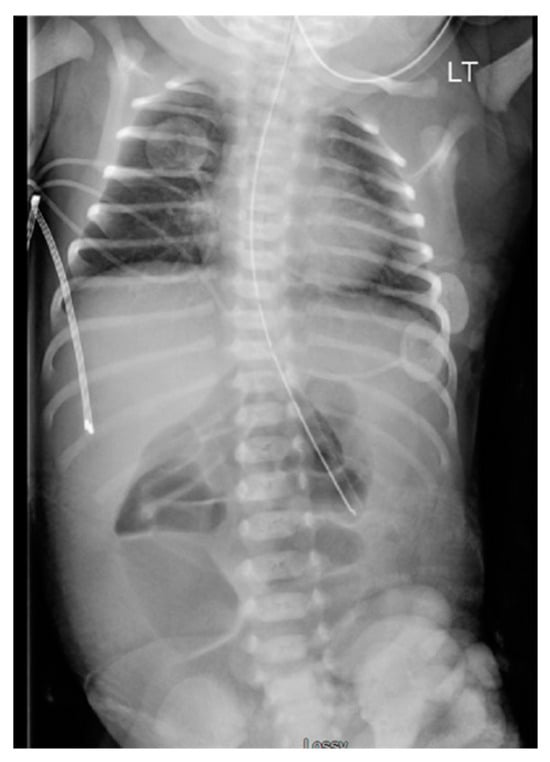

Initial management involved placing sterile saline-soaked gauze on the exposed bowel and wrapping it with a sterile bag. The infant was admitted to the Neonatal Intensive Care Unit, where an abdominal X-ray (AXR) revealed dilated intestines (Figure 2). The infant was given preoperative antibiotics (Ampicillin and Gentamycin).

Figure 2. Day 1 abdominal X-ray revealing dilated intestines.